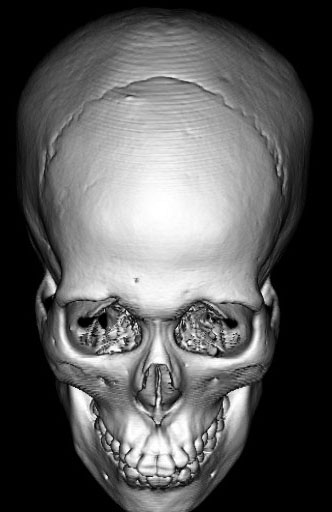

全脳照射後の頭蓋骨の部分的発育不全

2歳くらいで全脳照射を受けた子どもが15歳になりました。前頭骨だけの発育が悪くて額の間がとても狭くて,コメカミの凹みが目立つようになりました。両側の側頭部にチタンプレートを入れて額を広くして頭蓋形成をして,見栄えはとても良くなりました。このような手術を整容的頭蓋形成術といいます。